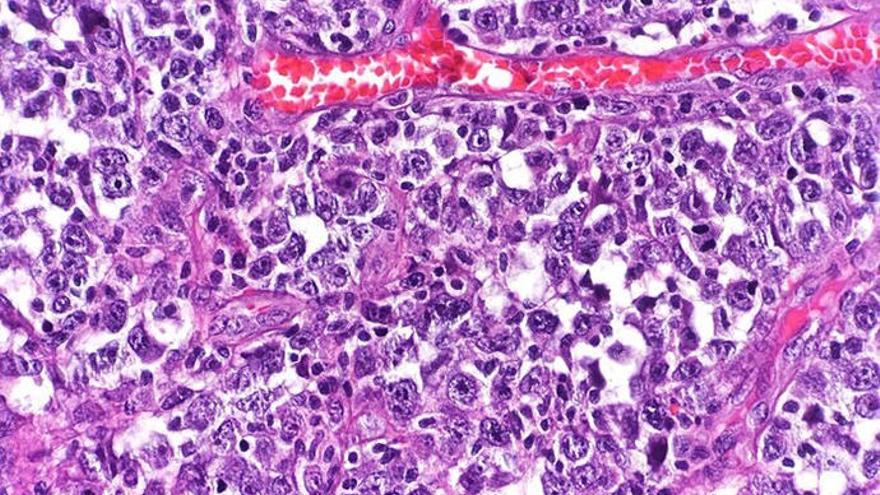

Los linfomas son un tipo de cáncer en la sangre que comienza en las células del sistema linfático y para los que resulta efectivo el tratamiento con CAR-T.

"Seleccionamos estos linfocitos T del mismo paciente y los dotamos de un 'arma' para que, cada vez que detecte uno de los antígenos CD30 -los que expresan las células tumorales del linfoma -, las elimine", ha detallado el responsable clínico del proyecto de CAR-T de Sant Pau, Javier Briones.